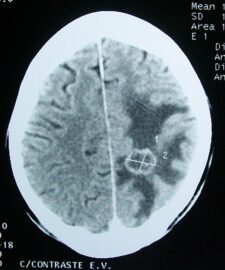

V štúdii CERENAT sa zistilo významné zvýšenie rizika rakoviny mozgu v dôsledku používania mobilných telefónov celkovo s 8-násobným zvýšením rizika pri vyššej expozícii v mestách.

Štúdia CERENAT potvrdzuje významné riziká gliómu spojené s vystavením rádiofrekvenčným poliam, ktoré uvádzal švédsky tím a štúdia INTERPHONE zahŕňajúca 13 krajín, a dodáva váhu epidemiologickým dôkazom, že rádiofrekvenčné polia, ktoré Medzinárodná agentúra pre výskum rakoviny v roku 2011 klasifikovala ako karcinogén skupiny 2B (možný), by sa mali preklasifikovať ako karcinogén skupiny 2A (pravdepodobný).